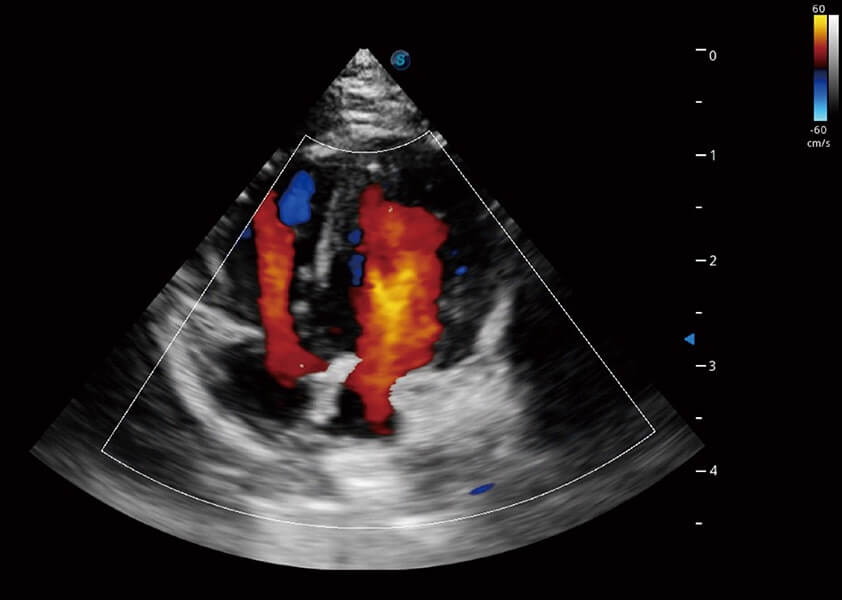

ProPet 60 作为一款高端台式动物超声设备,为动物医生的日常诊断提供了一系列贴合动物临床需求、解决临床实际问题的高级成像功能。凭借全系列高清探头,满足医生对腹部、心脏、生殖、浅表、肌骨等成像的所有需求,切实帮助您提升检查效率,提高诊断信心。

动物是人类最亲密的朋友和最值得信赖的伙伴。狗万官方网站也一直致力于探索动物专用的超声影像解决方案。 全新推出的ProPet系列,是狗万官方网站在动物超声影像智能化、专业化、精准化的一次跨越式革新。动物不能用言语来表述自己的不适,通过超声影像,ProPet系列搭建了动物医生与不同物种沟通的“桥梁”,为动物医生注入了“治愈之力”。